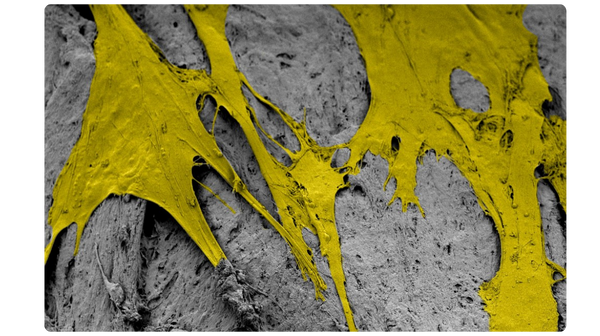

Scanning electron microscopy (SEM) at 3000x magnification. Images were pseudo colored in Adobe Photoshop to distinguish the cells (in yellow) from the fibers.

Optimized Handling

The interlocking fiber microhooks in PliaFX grafts provide optimized handling characteristics.4,5,7,8† The fibers interlock to provide a moldable, intact graft that easily transfers to the surgical site, conforms to the surgical site, and resists migration.4